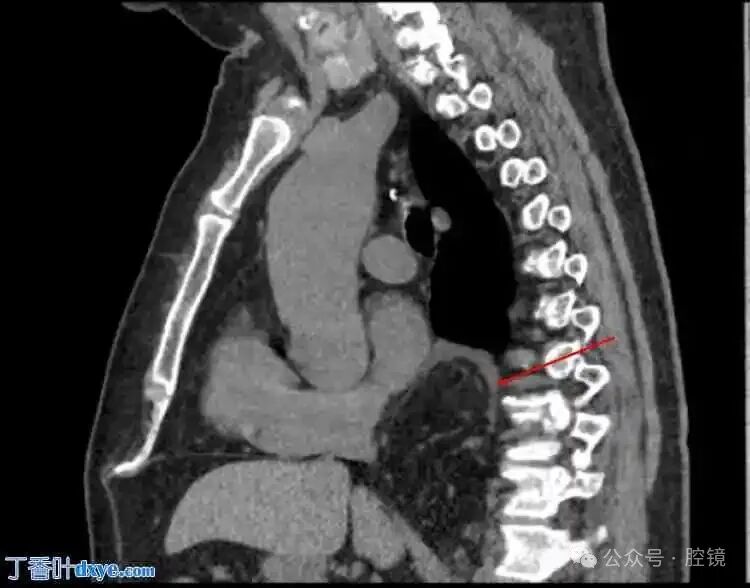

Figure 2. Sagittal view of the mass behind the heart.

Figure 4. Sagittal view: the herniated area is located on the dorsal side of the diaphragm.